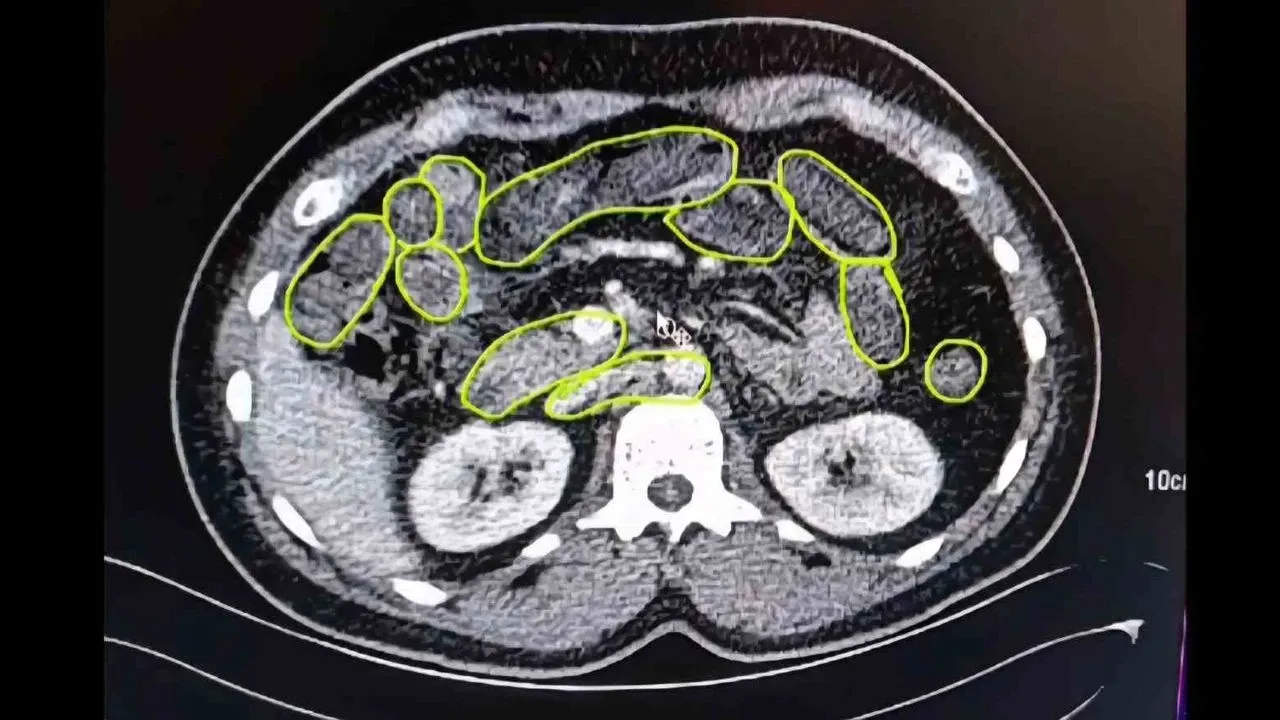

Uşak Eğitim ve Araştırma Hastanesi'ne götürülen şüphelilerin röntgen ve tomografi çekiminde mide ve bağırsaklarında kapsüller olduğu belirlendi.

Şüphelilerin yuttuğu 93 kapsülden 1 kilo 70 gram sentetik uyuşturucu çıkarıldı.